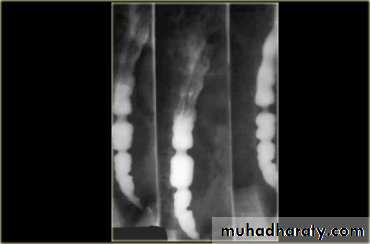

tertiary contractions

Diffuse esophageal spasm

Diffuse esophageal spasm produces intermittent contractions of the mid and distal esophageal smooth muscle, associated with chest symptoms• Congenital Anomalies